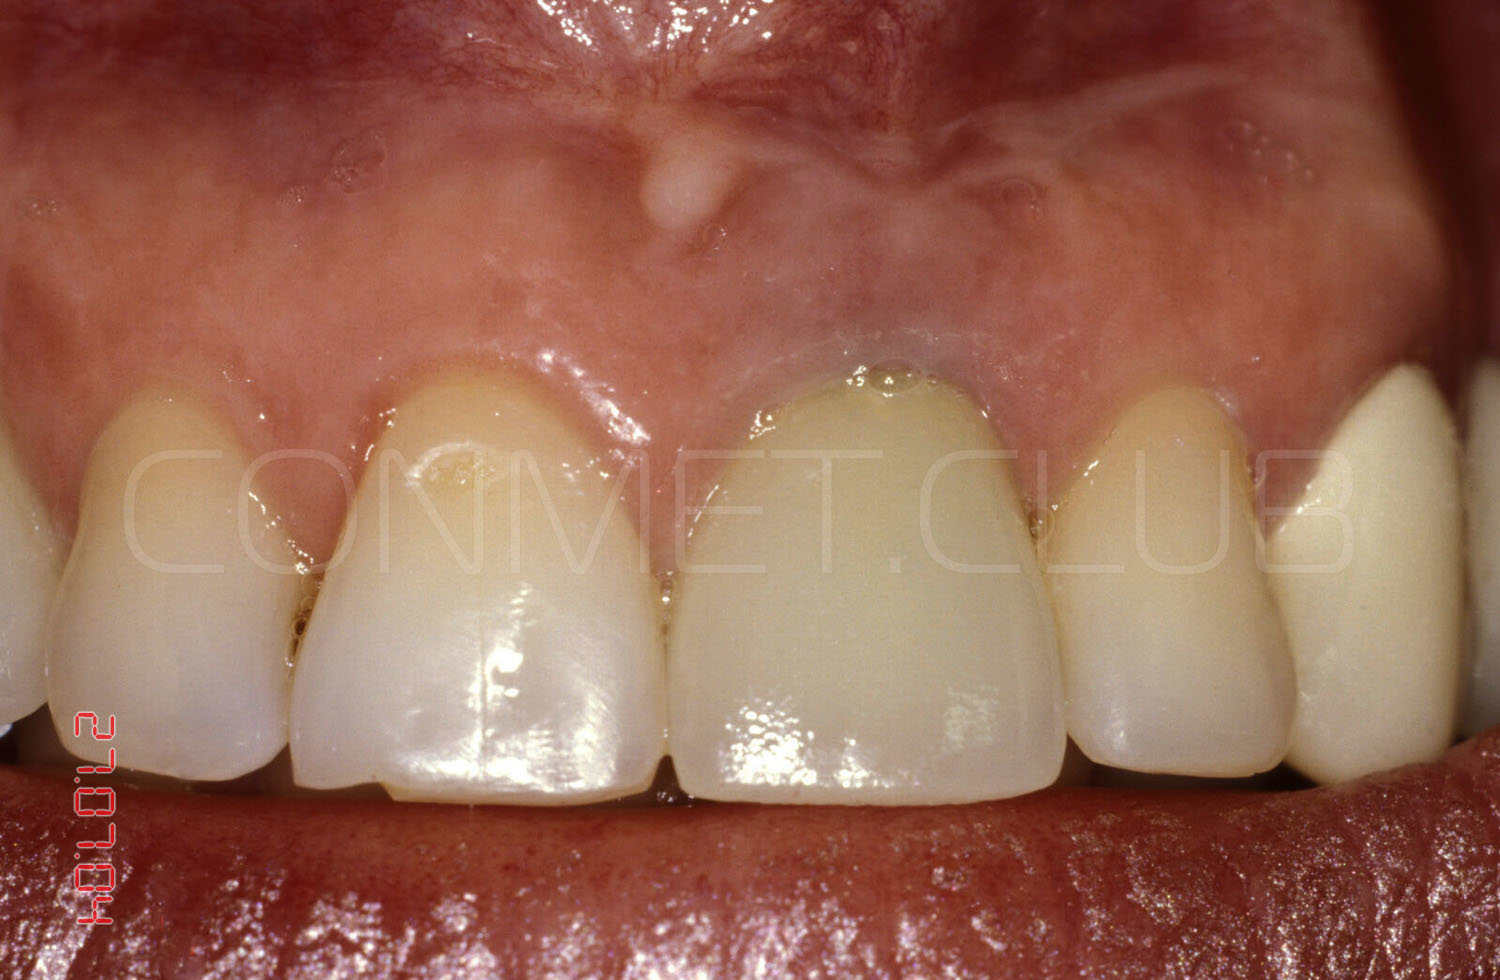

Контрольное фото через 6 недель после окончательного протезирования. Почти идеальная сохранность межзубных сосочков.

Итоговое фото через 6 недель после окончания протезирования.

Ситуация в полости рта через 10 лет после операции. Обратите внимание на сохранность межзубных сосочков около имплантата и полное отсутствие рецессии десны на поддесневой, полированной части имплантата.